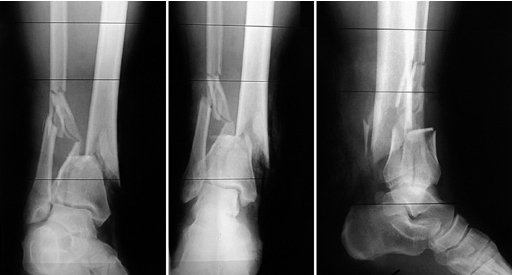

51-year-old man